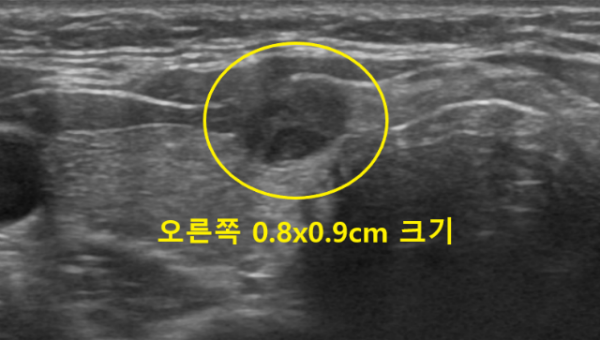

갑상선초음파상 오른쪽 갑상선에 가로x세로의 길이가 약 0.8x0.9cm 크기의 저에코성 결절이 관찰되었습니다. 모양은 타원형이었으나 경계가 일부 희미하게 보이는 양상의 비특정형 결절로 판단되었습니다.